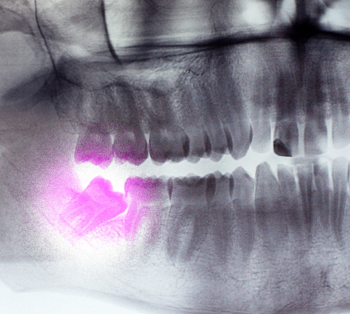

דף הבית מגזין שיני בינה מגזין שיני בינה כמה זמן מחכים לעקירת שן בינה בבית חולים? ומה אפשר לעשות בינתיים קיבלתם הפניה לבית חולים לעקירת שן בינה? כך תקצרו את זמן ההמתנה המיומנות הכירורגית ששומרת על בריאות הפה שלכם הרדמה כללית וטשטוש (סדציה) בעקירות שיני בינה – המדריך המלא המדריך המקיף של כירורג פה ולסת פתרונות כירורגיים לפה ולסת – שיניים מורכבות תחת טיפול מקצועי מה זה רופא פה ולסת? המדריך המלא איך יודעים אם העקירה מורכבת? סימנים שמעידים על צורך בטיפול כירורגי זקוקים לעקירת שן בינה דחופה? אנחנו כאן בשבילכם! כיצד לבחור רופא פה ולסת לטיפול מורכב? כירורג פה ולסת: המומחיות הכירורגית ששומרת על בריאות הפנים והלסתות מה עושה מומחה פה ולסת? מדריך למטופל מחיר לעקירת שן בינה – כל מה שצריך לדעת כל המידע הרלוונטי על עקירת שיני בינה חמשת הנקודות החשובות על עקירת שיני בינה כלואות כירורג פה ולסת או רופא שיניים, מה ההבדל ומתי לפנות למומחה? מהי עקירה כירורגית, ובאילו מקרים יש בה צורך? איפה עושים עקירת שן בינה? 5 עובדות על נשים, שיני בינה, ומה שביניהן דלקת בשן בינה – הגורמים, התסמינים ואופן הטיפול הגורמים ודרכי הטיפול לשן בינה כלואה היתרונות בעקירה כירורגית של שיני בינה במרפאה פרטית לעומת בית חולים האם לעקור שיני בינה? האם ניתן למנוע הוצאת שיני בינה?בעוד שאת הצורך בהוצאת שיני הבינה לא ניתן למנוע, שכן מרכיבים כמו גודל הלסת, גודל השיניים, המרווח בקשת השיניים ועוד אינן... החלמה מעקירת שן בינה, תופעות לוואי וסיבוכיםישנם תופעות לוואי וסיבוכים כלליים האופייניים לעקירות באופן כללי, ישנם סיבוכים שייתכנו לאחר הוצאת שיני בינה עליונות,... הרדמה מקומית או סדציה תוך וורידיתבעזרת זריקת הרדמה מקומית ניתן לעקור את שיני הבינה, אולם צריך לקחת בחשבון שבחלק גדול מהמקרים המטופל ירגיש את הטיפול. הקשר בין ציסטות גידולים ושיני בינה כלואותהטיפול בציסטות וגידולים סביב שיני הבינה תלוי במספר גורמים הכוללים את המראה הרנטגני של הממצא, סוג הנגע, המיקום שלו, העדפת... האם תמיד צריך לטפל בשיני בינה? מומחה פה ולסת עונהשיני בינה שצמחו באופן תקין לקשת השיניים – אין צורך לעקור. שיני בינה עם עששת עמוקה או כאלה שגרמו לזיהום – יש צורך לעקור... כירורג פה ולסת, מתי לפנות למרפאה להוצאת שיני הבינה?ההחלטה לגבי מי הרופא הנכון ביותר לעקור את שן הבינה משתנה בהתאם למורכבות המקרה, המצב הבריאותי של המטופל, וכמובן ההעדפה...